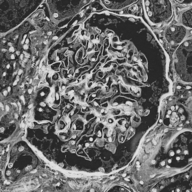

Image datasets in digital pathology applications often consist of consecutive slides stained differently, each staining providing specific information on the same region of interest (see Figure 1, first row). Even though differently stained slides appear very different, there is often a significant amount of consistent information between them. For example, they may both share the same counterstain (e.g. haematoxylin), or they may highlight different parts of the same structure.

Objects to be segmented, e.g. glomeruli, are generally easily identified between stainings as globally they exhibit the same structure and texture, see Figure 1. It should therefore be possible to bias the network to learn stain invariant features. This work investigates this possibility by modifying the data presented to the network in an unsupervised manner. Borrowing domain adaptation terminology, herein the staining used for training and validation is referred to as as the source staining (irrespective of any transformations), and the stainings to which the network are applied as target stainings.

The last strategy, named Colour Transfer, restricts this to within meaningful bounds at the expense of being more complicated. The colour profile of each training patch is replaced with that of a randomly selected staining during training with probability , where is the number of stainings in the dataset. Therefore each ‘staining’ (including the source) is presented to the network with equal probability. The colour transfer is achieved by deconvolving the patch and applying its stain concentrations to stain vectors taken from another staining. Various approaches to this exist [16, 17, 18] (including computer vision approaches [19]), in this work we use that proposed by Macenko et al. due to its simplicity (automatic determination of stain vectors) and realistic output (see Figure 1, bottom row). It is necessary, however, to have samples of the target stainings to determine their stain vectors (this requirement can be removed by using predetermined stain vectors and Ruifrok and Johnston’s approach [15]). During training, a random patch from a random target staining is selected and the target stain vectors are determined.

N.B. the intention is to present plausible colour profiles to the network. This does not necessarily correspond to biologically relevant image information but is explored for any potential for the tested staining modalities. Potential limitations are addressed, e.g. in Figure 1 the bright red colour (chromogenic reaction used to detect CD34, a marker of blood vessel inner lining) could be successfully transferred but it is not localised as in the original image.

Next is a strategy to extract biological information that is consistent across different stainings—the haematoxylin counterstain. Despite this biological plausibility, it does not result in good results. Indeed, the haematoxylin transformed images vary greatly between the different stainings (see Figure 1, second row). Several factors may explain this: 1) haematoxylin’s concentration relative to the primary stain may vary from one staining to another, resulting in different shades of blue and fixation amount; 2) as a counterstain, haematoxylin may become mixed with another stain in structures that are targeted by both. These result in a color mixing that is in practice not perfectly unmixed by a color deconvolution algorithm.